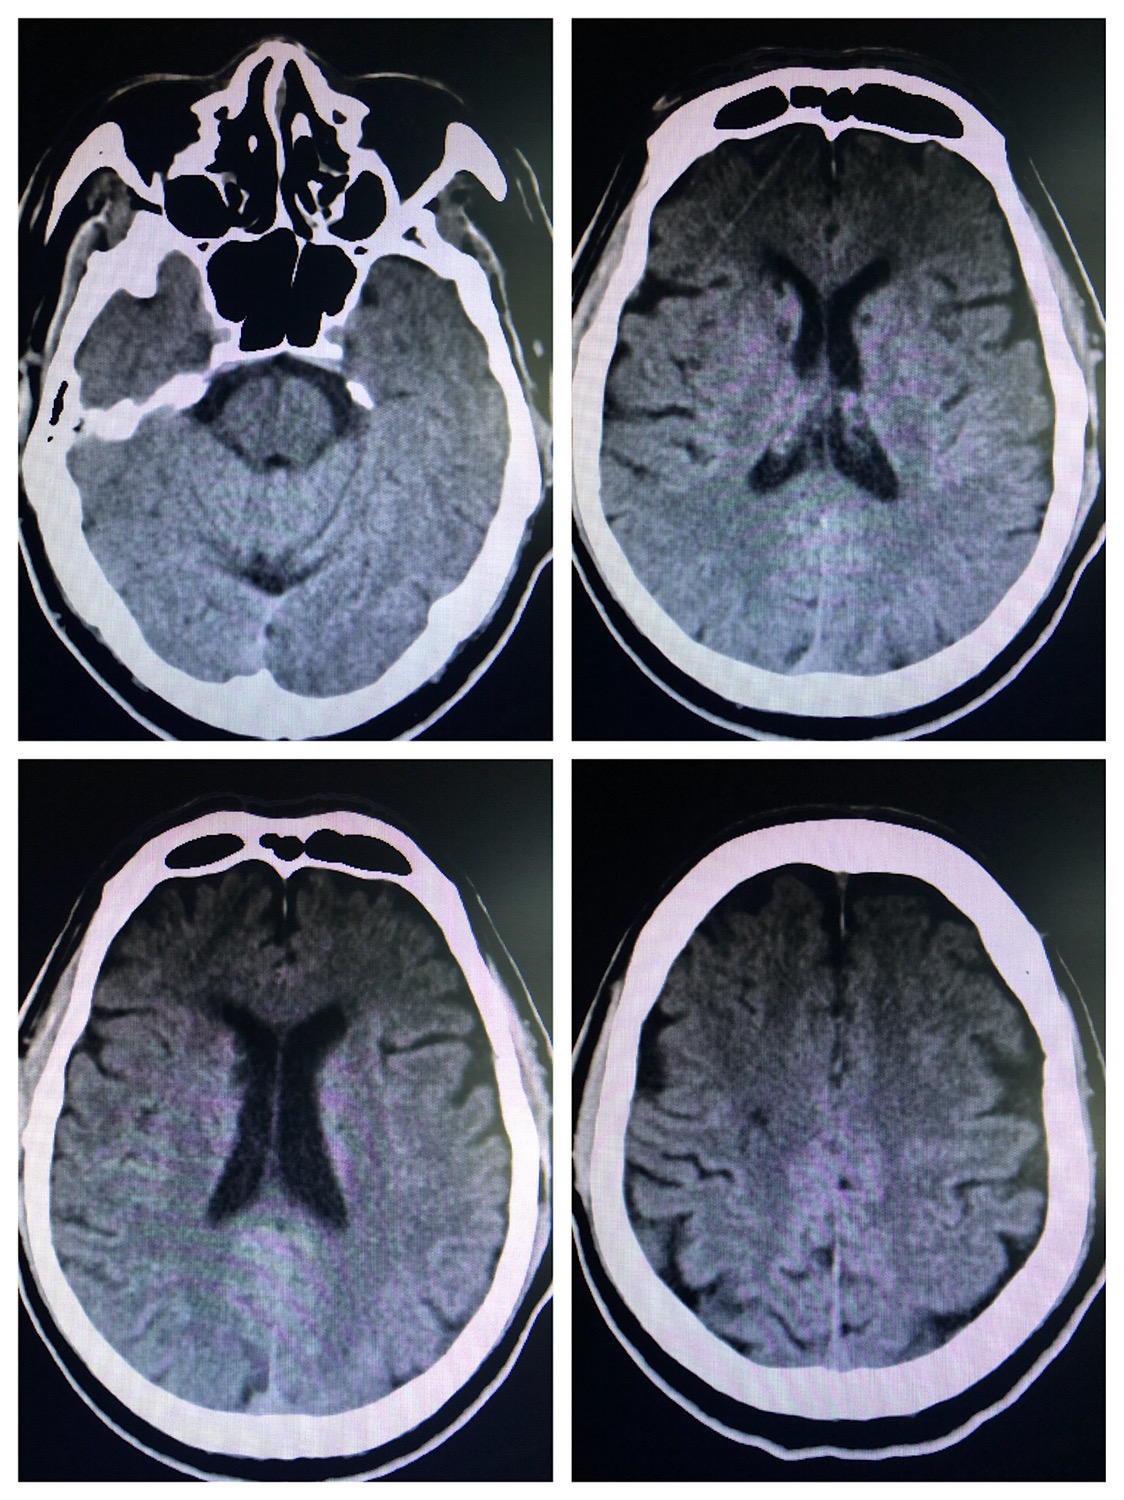

头CT示左侧小脑半球,右侧半卵圆中心及双侧基底节多发腔隙性脑梗死。

核磁示:右侧半卵圆中心新发腔隙性脑梗死,颅内多支血管狭窄,双侧胚胎型大脑后动脉。